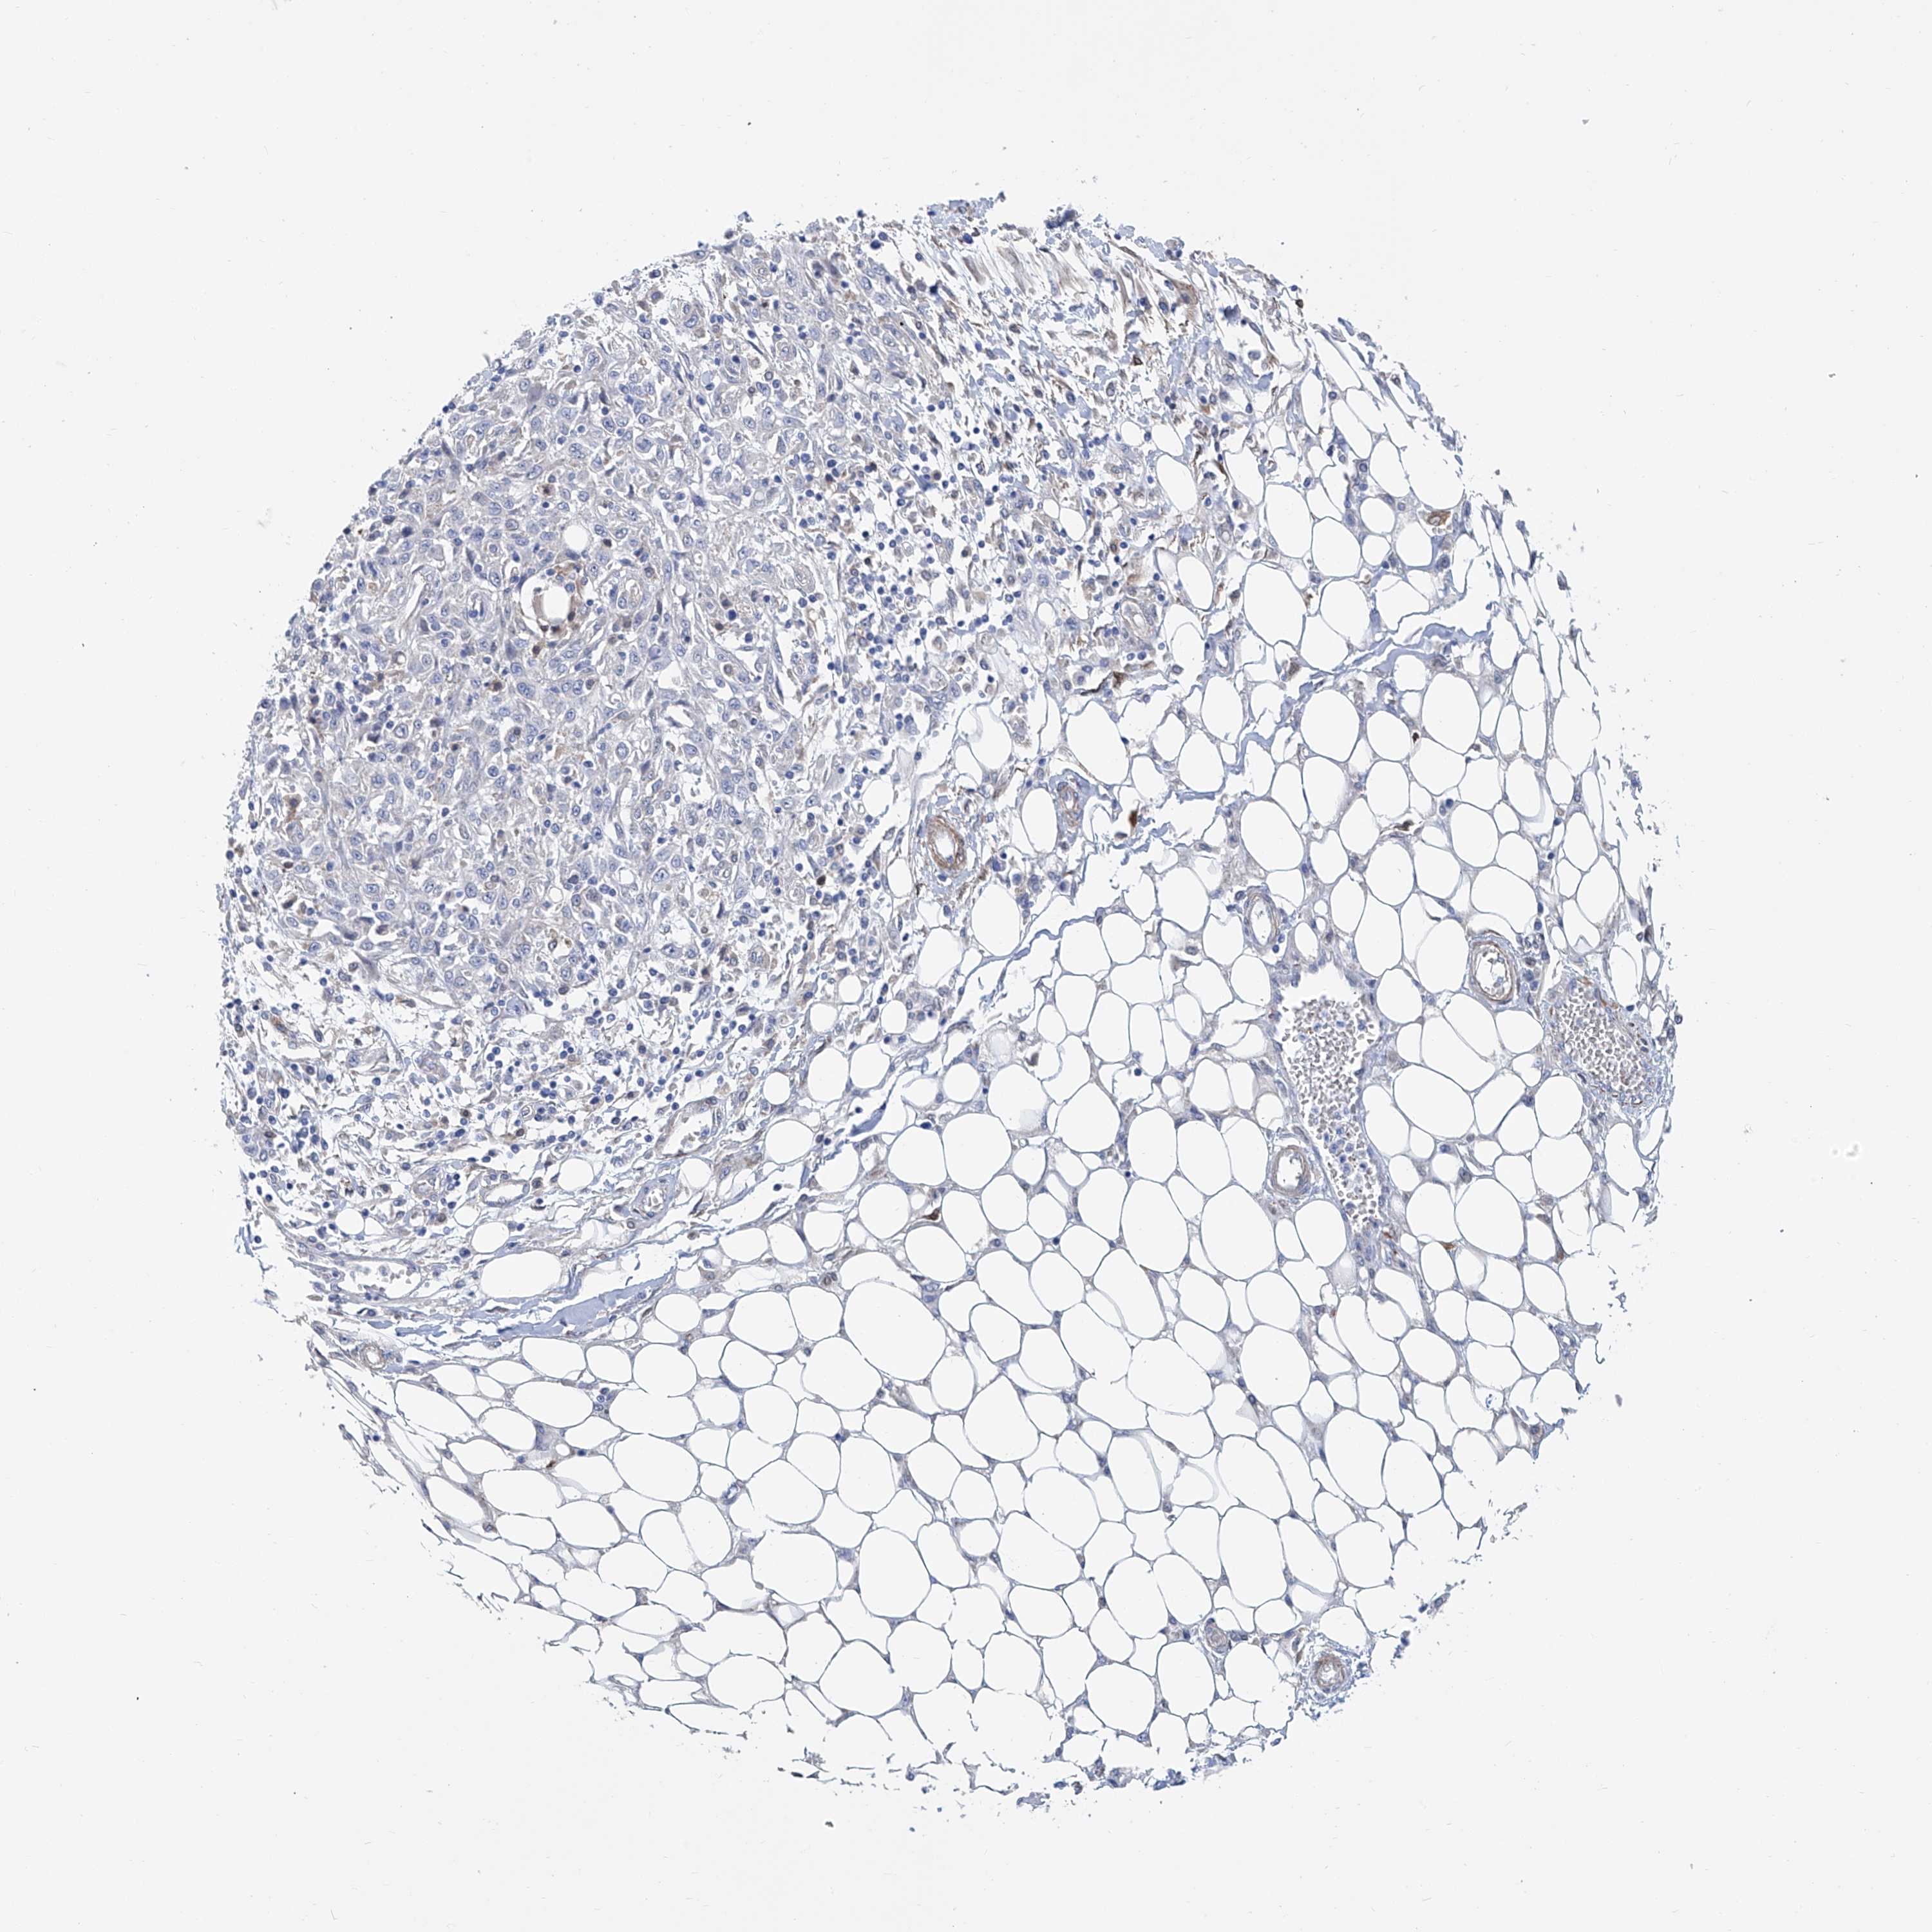

SKIN CANCER - Protein expressioni

A mouse-over function shows sample information and annotation data. Click on an image to view it in a full screen mode. Samples can be filtered based on level of antibody staining by selecting one or several of the following categories: high, medium, low and not detected. The assay and annotation is described here.

Antibody staining in the annotated cell types in the current human tissue is reported as not detected, low, medium, or high, based on conventional immunohistochemistry profiling in selected tissues. This score is based on the combination of the staining intensity and fraction of stained cells.

Each image is clickable and will lead to virtual microscopy that enables deeper exploration of all samples and also displays staining intensity scores, fraction scores and subcellular localization as well as patient and tissue information for each sample.

Antibody HPA026764

Not detected

Negative

None

Basal cell carcinoma